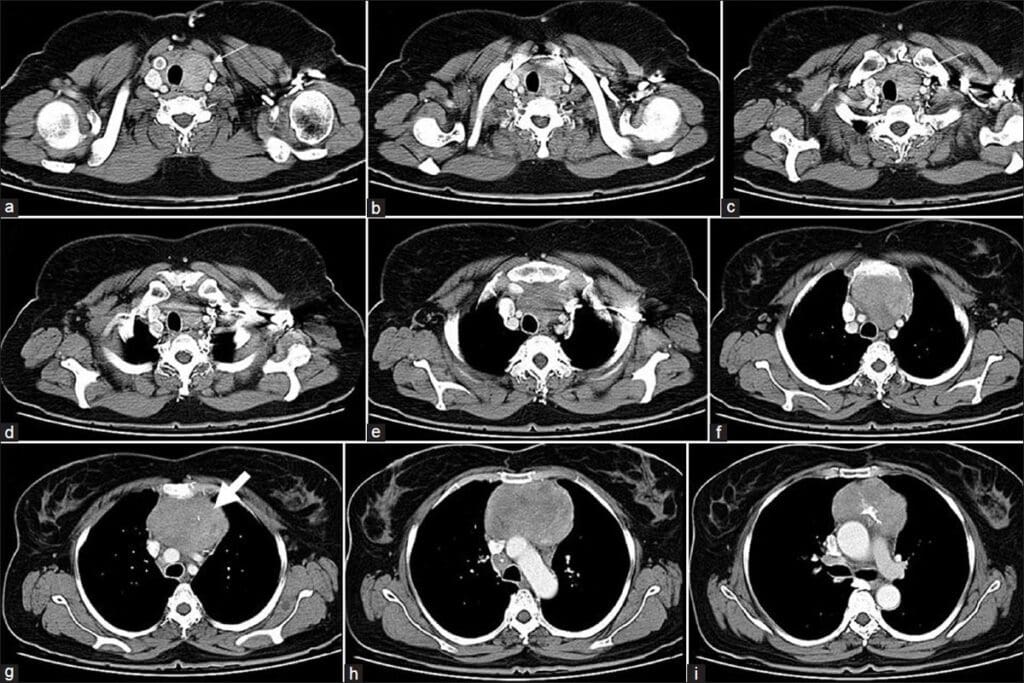

Acute Pyelonephritis

Acute pyelonephritis is an infection in the kidney, usually from bacteria. On CT urograms, it shows as renal enlargement with patchy or striated nephrograms. You might also see perinephric stranding, which means inflammation spreading beyond the kidney.

Emphysematous Pyelonephritis

Emphysematous pyelonephritis is a severe kidney infection, common in diabetics. CT scans show gas in the renal parenchyma and sometimes in the collecting system or perinephric space. It’s a serious condition that needs quick diagnosis and treatment.

Renal and Perirenal Abscesses

Renal and perirenal abscesses are pus collections in or around the kidney, caused by infections. On CT urograms, they look like low-attenuation masses with rim enhancement. Perirenal abscesses can push against or compress nearby structures.

Xanthogranulomatous Pyelonephritis

Xanthogranulomatous pyelonephritis is a long-term inflammatory kidney condition, linked to obstructive uropathy and infection. CT scans show renal enlargement, calculus, and multiple low-attenuation areas in the kidney, which are xanthogranulomatous tissues.